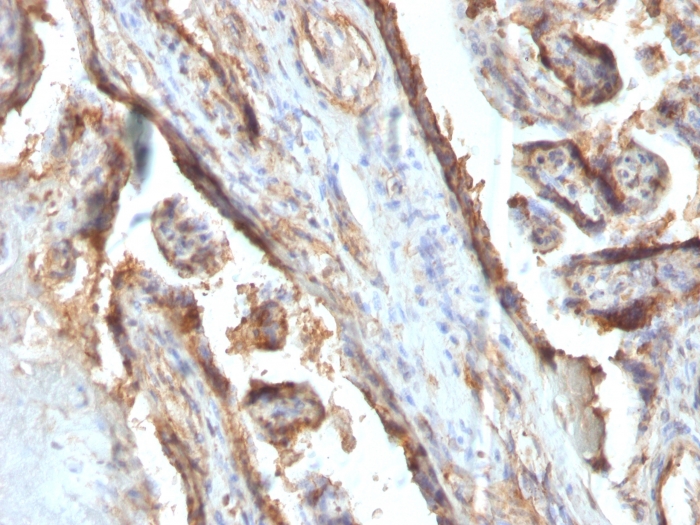

Formalin-fixed, paraffin-embedded human Placenta stained with Galectin-13 Monoclonal Antibody (PP13/1161).

It recognizes a 32kDa protein, which is identified as homodimer of galectin-13 (also known as PP13). Galectins are a family of soluble -galactoside-binding lectins that modulate cell-to-cell adhesion and cell-to-extracellular matrix (ECM) interactions and play a role in tumor progression, pre-mRNA splicing and apoptosis. One such member, galectin-13, is a 139 amino acid protein that contains one galectin domain. Possessing lysophospholipase activity, galectin-13 exists as a disulfide-linked homodimer. Galectin-13 is suggested to have a developmental role in the placenta and may display immunobiological activity in feto-maternal blood-spaces. Screening for galectin-13 in maternal serum during the first trimester of pregnancy may serve as a diagnostic marker to predict preterm pre-eclampsia.